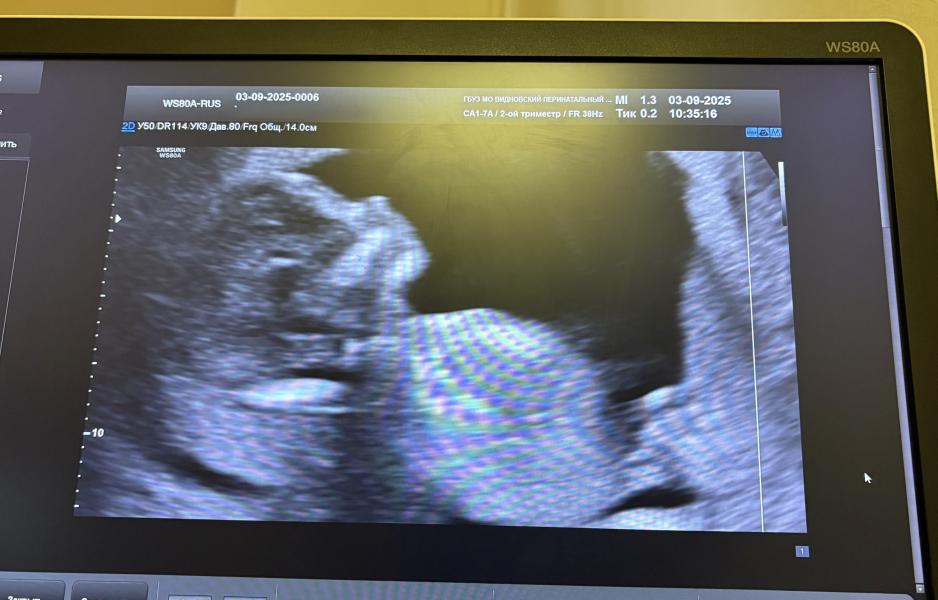

Во время узи малышок показал всё, кроме профиля - носик спрятал и спал. Отправили покушать сладкое, но и через двадцать минут ничего не поменялось. Врач попалась премилая, снова отправила перекусить и смотрела меня уже третий раз, убеждая нашу козявку всё же проснуться и показаться 😅 на секунду повернулся в профиль и снова задрых! Такой маленький, а уже такой жучок, весь в своего папу))

Все показатели в абсолютной норме, срок с 13.4 превратился в 14.3. Врач сначала увидела пол чётко, а потом засомневалась и не стала озвучивать. А нам и не важно, мы вообще думаем узнать прям на родах 😅